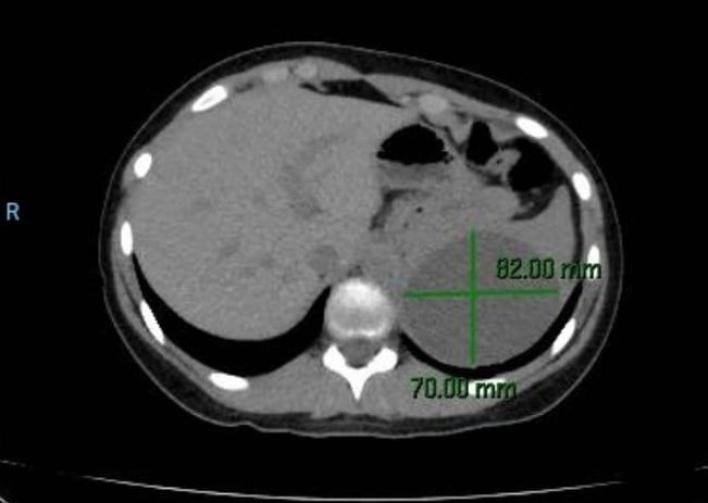

En guardia fue evaluada por el Servicio de Cirugía General Pediátrica. Al momento de la consulta el abdomen era blando, depresible e indoloro. No sé palpaban organomegalias. Se solicitó tomografía computarizada que informaba la presencia de un quiste esplénico de 80 x 70 mm (Figura 1 y Figura 2) y laboratorio para Hidatidosis (IFI – inmunofluorescencia indirecta).

Figura 2: Tomografía computarizada diagnóstica. Corte axial